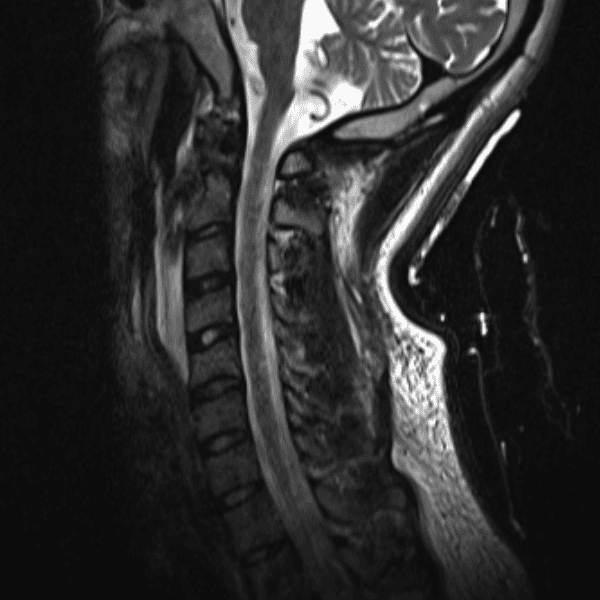

Simulates call by including subtle or difficult cases and some normals.

35 cases